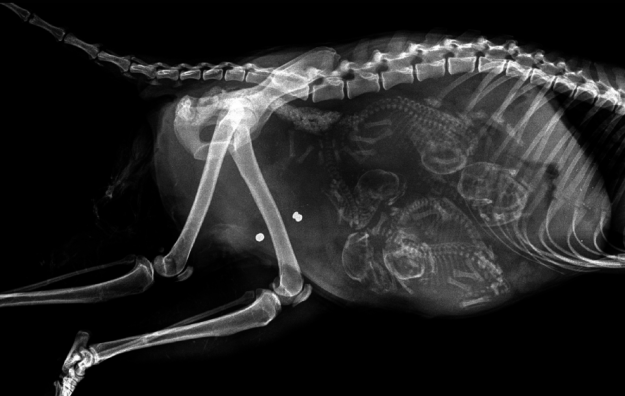

Еще одна беременная кошка.